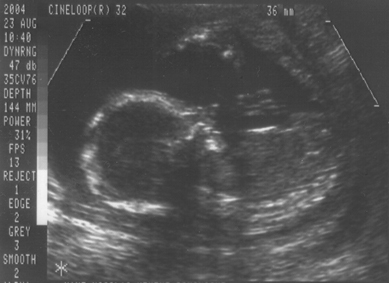

23. August 2004 (Ein Mädchen !)